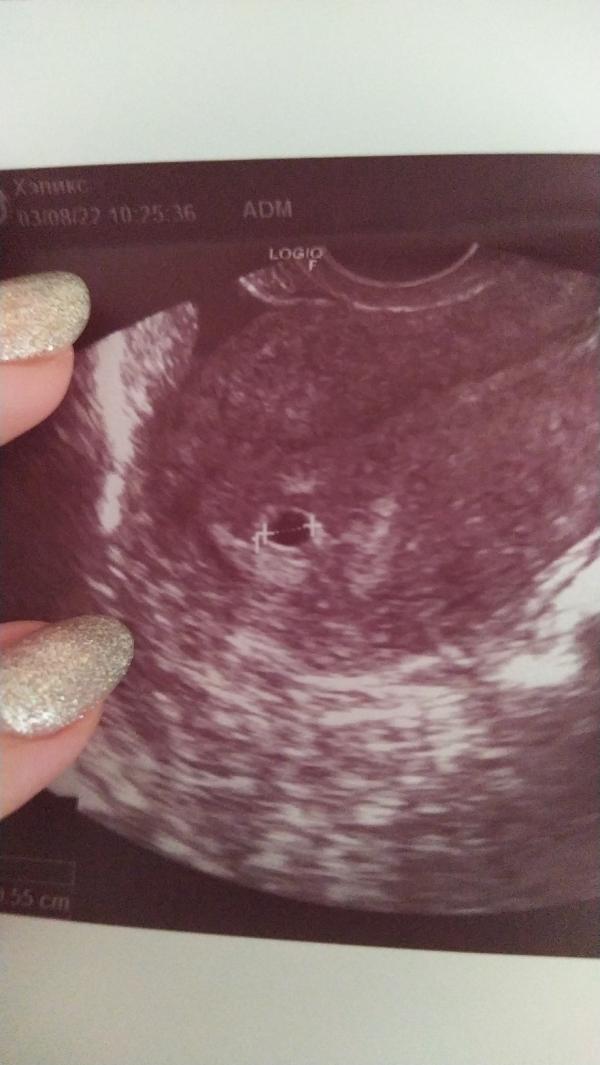

Первое УЗИ: что увидели на скрининге? Делимся опытом и впечатлениями о первом УЗИ малыша!

Всем привет! Наше первое УЗИ, еще минипузырëк😍

Поздравляю а на какой день задержки делали узи? Когда последние кд были?😊

Спасибо) последние кд 29.06 задержки 8 дней. 😊

@berta.miss2017, сердечко ещё не слышно?

@malishka_87 на УЗИ в 8 дней задержки ещё ничего не было, через две недели уже тутухает😊